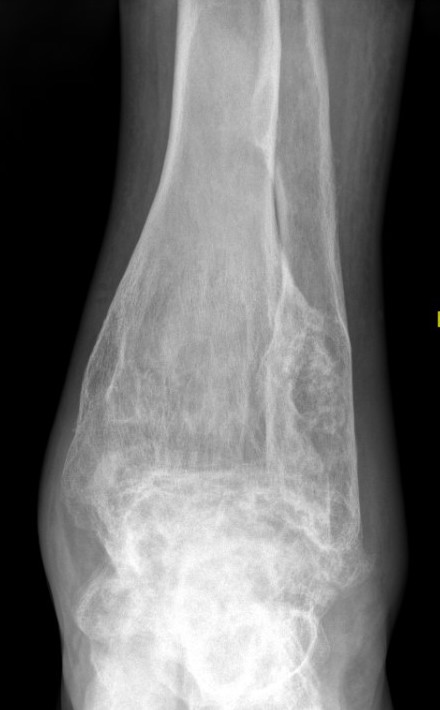

Intramedullary lucent diaphyseal lesion with 'ground glass appearance'

- thinned, slightly bulged cortex

- ± endosteal scalloping

- may have angular deformity / bowing

Sabre tibia

Pathological fracture